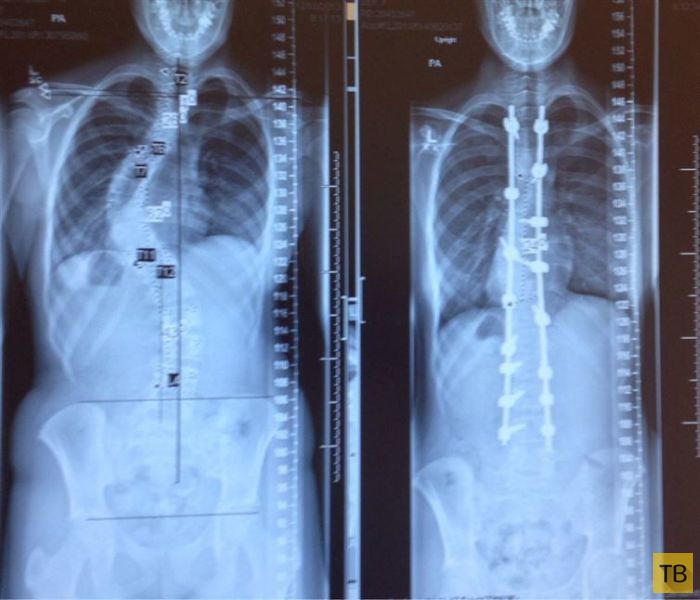

Рентгеновские снимки до и после лечения сколиоза

Рентгеновские снимки до и после лечения сколиоза